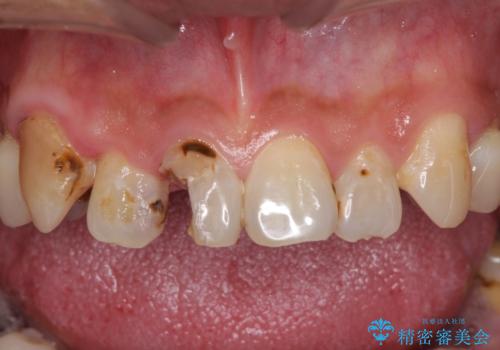

- 前歯や奥歯の虫歯を放置しており、それらの治療を契機に真っ白な歯にしたいとのことで来院された患者様です。

咬み合わせを改善するに当たって、抜歯しなければならない歯や歯列の改善が必要な箇所があったため、矯正治療やインプラント治療から始めていくこととしました。

不自然なくらい真っ白にしたいとのことでしたので、透明感のないフルジルコニアクラウンを用いて補綴することとしました。